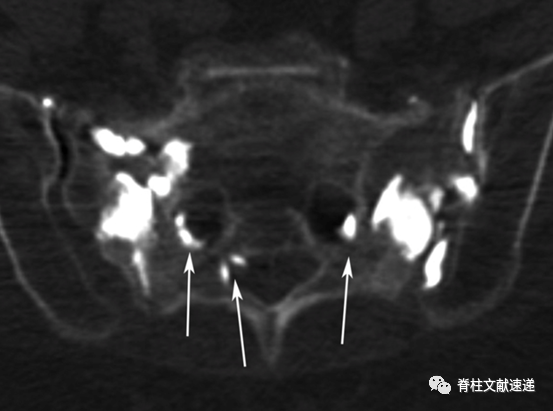

骶骨成形术手术操作:透视下将13G穿刺针置入骶后孔和骶髂关节中间的骶骨翼,与骶髂关节成45度,侧位上位于骶骨正中,一侧可以置入2-3根穿刺针,以保证骨水泥分布均匀,注入骨水泥时正位片上观察,避免骨水泥向内侧延伸,如下图所示。手术操作较胸腰椎椎体成形容易。

文献中描述了两例骶骨成形术相关骨水泥渗入神经孔的病例,如下图。有一过性 S1 神经炎,在经椎间孔硬膜外注射类固醇后消退。